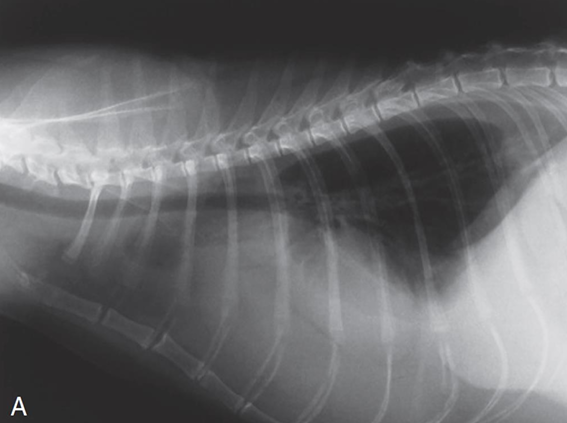

![]() | Pneumothorax - 폐가 쪼그라들면서 하얗게 보임 - 심장이 떠 있음 |